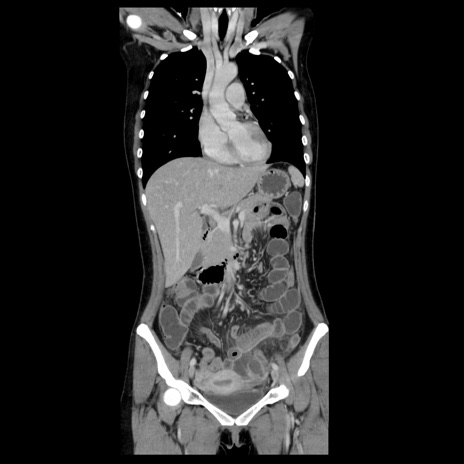

【症例】40歳代女性

【主訴】上下腹部痛

【現病歴】2日目から下腹部痛あり。夜間は痛みで眠れなかった。昨日より上腹部痛と下痢が出現。臥位で痛みは軽快したため、休んでいた。本日になって臥位でも立位でも痛みが強くなってきたため救急要請。

【既往歴】子宮内膜症

【身体所見】部:平坦・軟、左上下腹部に圧痛あり、反跳痛あり。

【データ】WBC 21800、CRP 26.78

CT